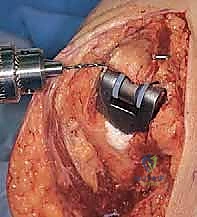

يتم إبعاد العضلات والأربطة بلطف للوصول إلى المفصل. يقوم الجراح بإزالة الغشاء الزليلي الملتهب بالكامل (Synovectomy)، ثم يزيل الأسطح العظمية المتآكلة من نهايات عظم العضد وعظم الزند باستخدام أدوات جراحية دقيقة جداً.

يتم بعد ذلك حفر القناة النخاعية داخل عظم العضد وعظم الزند لتجهيز المساحة التي سيتم إدخال سيقان المفصل الصناعي فيها.

5. زراعة المفصل الصناعي (Implantation)

يتكون المفصل الصناعي من قطعتين معدنيتين رئيسيتين (جزء عضدي وجزء زندي) وبينهما مفصلة بلاستيكية (Hinge) توفر الحركة السلسة.

يتم تثبيت هذه الأجزاء المعدنية داخل القنوات العظمية باستخدام الأسمنت العظمي الطبي (Bone Cement)، وهو مادة خاصة تضمن تثبيتاً فورياً وقوياً، وهو أمر بالغ الأهمية لمرضى الروماتويد الذين يعانون من هشاشة العظام.